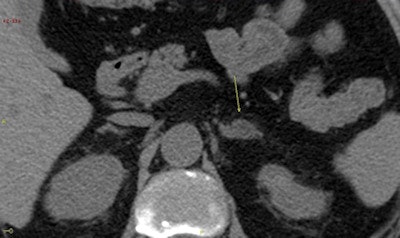

Although metabolic alterations and increased risk of CV event have been noted in patients with silent hypercortisolism (subclinical Cushing's syndrome), this is thought to be the first time that CV event incidence and mortality in the long term have been assessed in such patients.

Prior to the study, the lack of historical data about these tumors meant that there was no established treatment strategy for such patients, and their management differed from hospital to hospital, leading to high costs but varying results for patients, according to the authors.